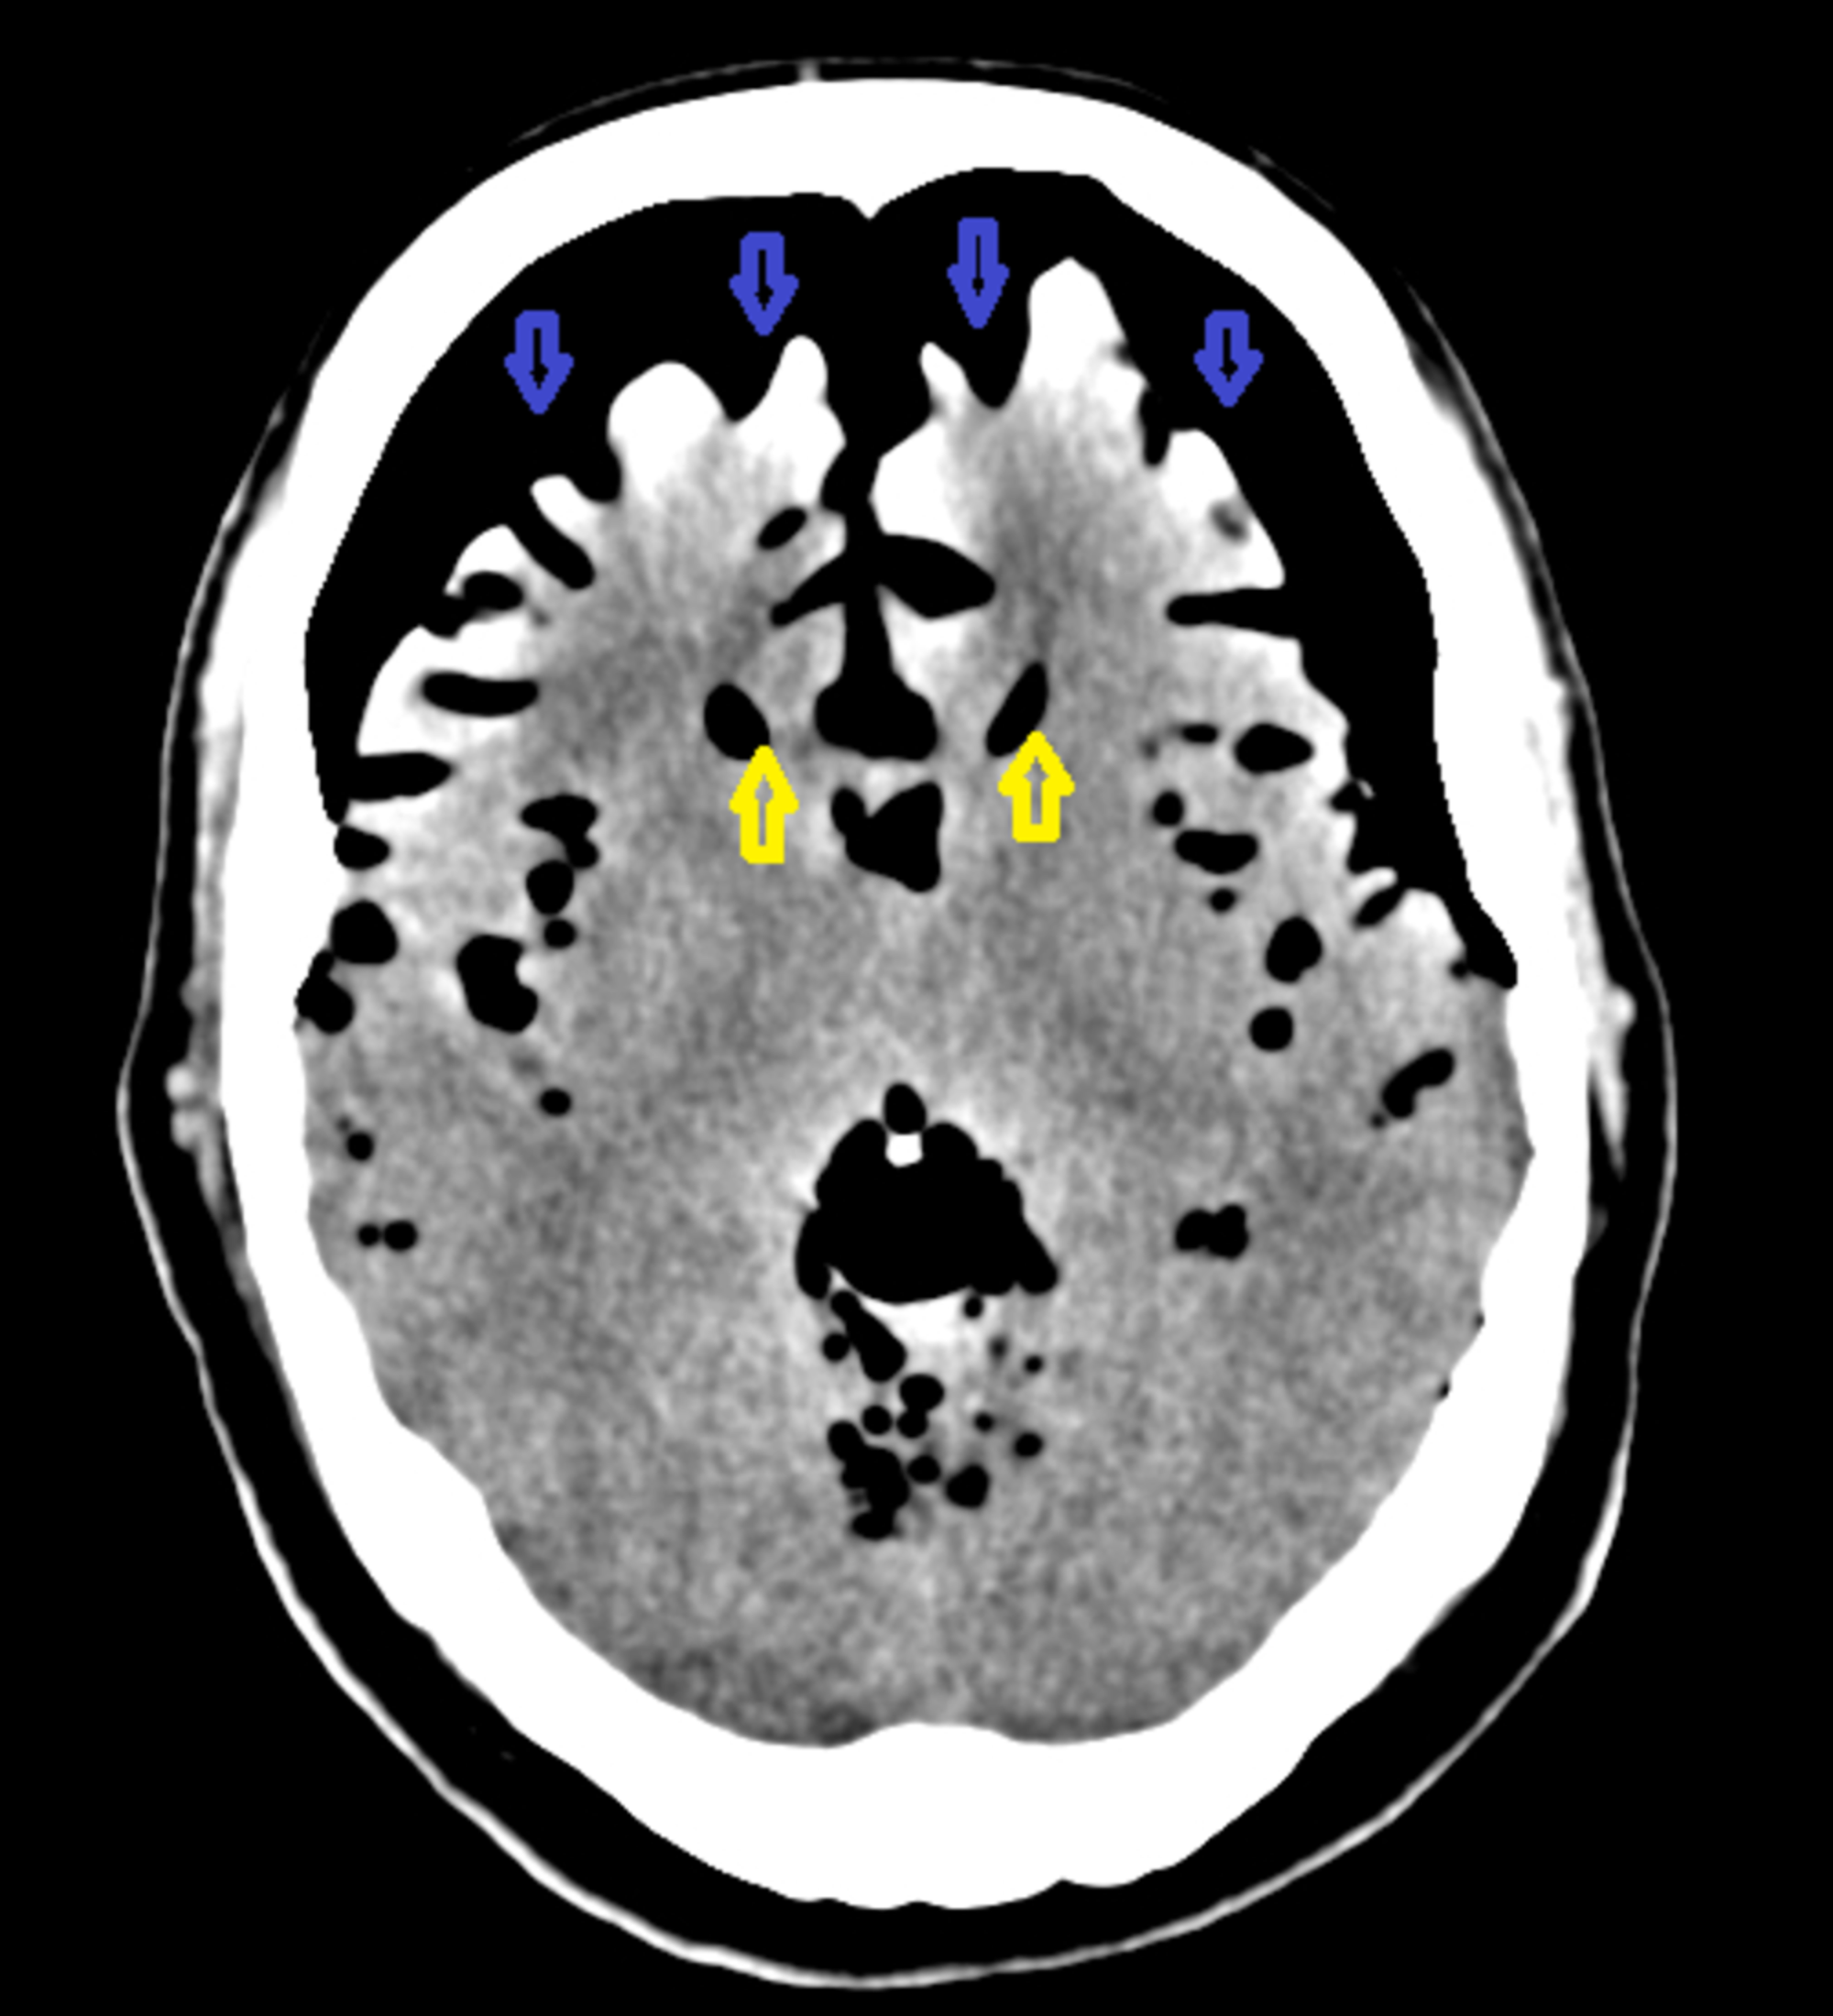

Mount Fuji Sign Tension Pneumocephalus Axial Non Contrast Brain Ct Download Scientific Diagram

www.researchgate.net